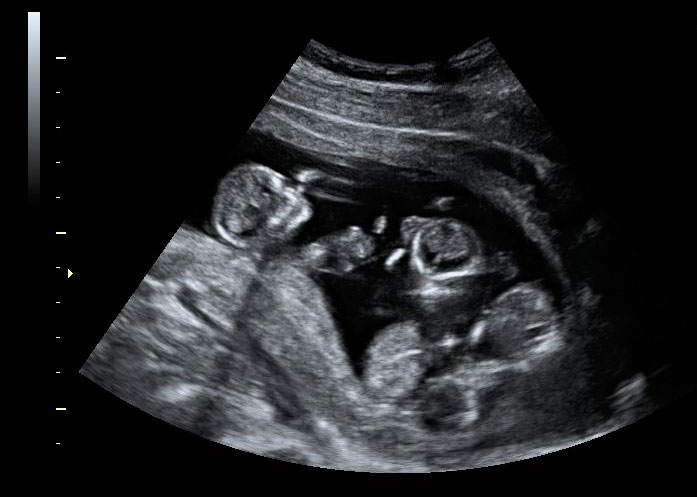

Ecografía Embarazo 4D Semana 12 - CRIBADO DEL PRIMER TRIMESTRE